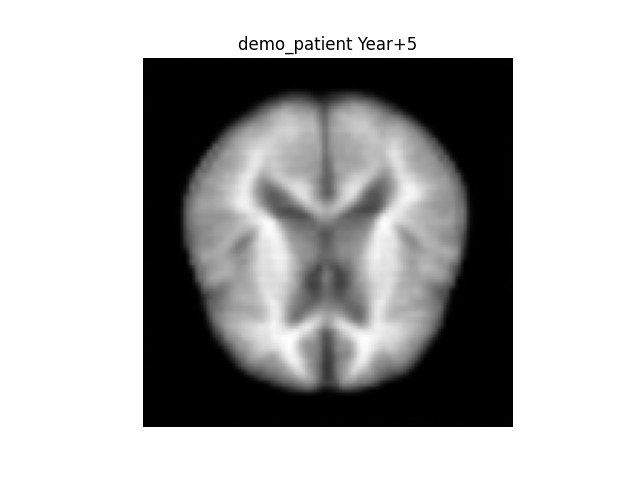

NeuroMirror-X generates a customized digital replica of the patient's brain from a single MRI scan. It: Transforms the MRI into a latent representation utilizing a CNN encoder. Employs a trajectory prediction network (CVAE + Transformer) to model the evolution of that embedding over time. Translates the forecasted embeddings into synthetic future MRI images (t+1 to t+5 years). Produces individualized Alzheimer’s risk assessments and Grad-CAM heatmaps that emphasize at-risk brain areas. This enables physicians and scientists to observe disease advancement and recognize early indicators for treatment.